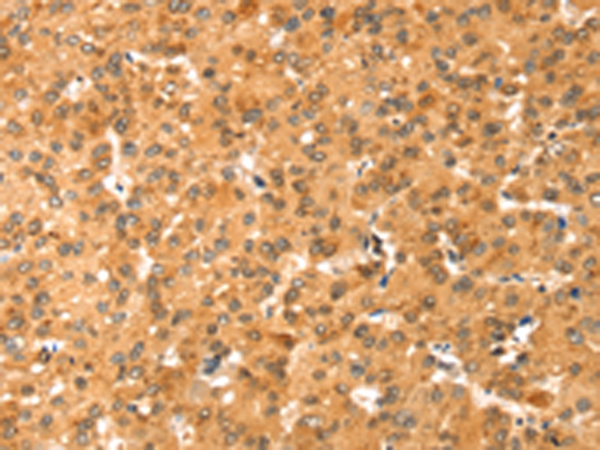

分类: 科研抗体货号: P07216别名: NOC4, COX4NB, C16orf2, C16orf4, FAM158B应用: WB,IHC反应种属: Human, Mouse, Rat